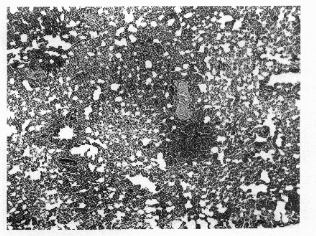

Figure 4. Interstitialpneumonia in aferret

immediately after clearance of microfi-

lariae from the peripheral blood x 100).